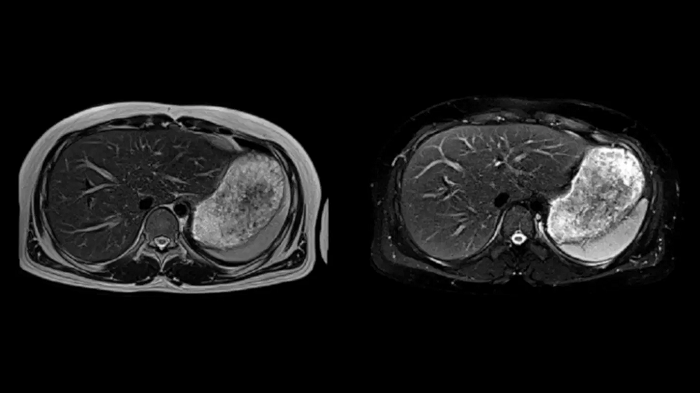

T2 BLADE

T2 motion insensitive abdominal imaging with BLADE results in outstanding outcomes, regardless of the orientation or if fat saturation is needed.

MAC-ID: 7aaaa0165. Image Credit: Siemens Healthineers